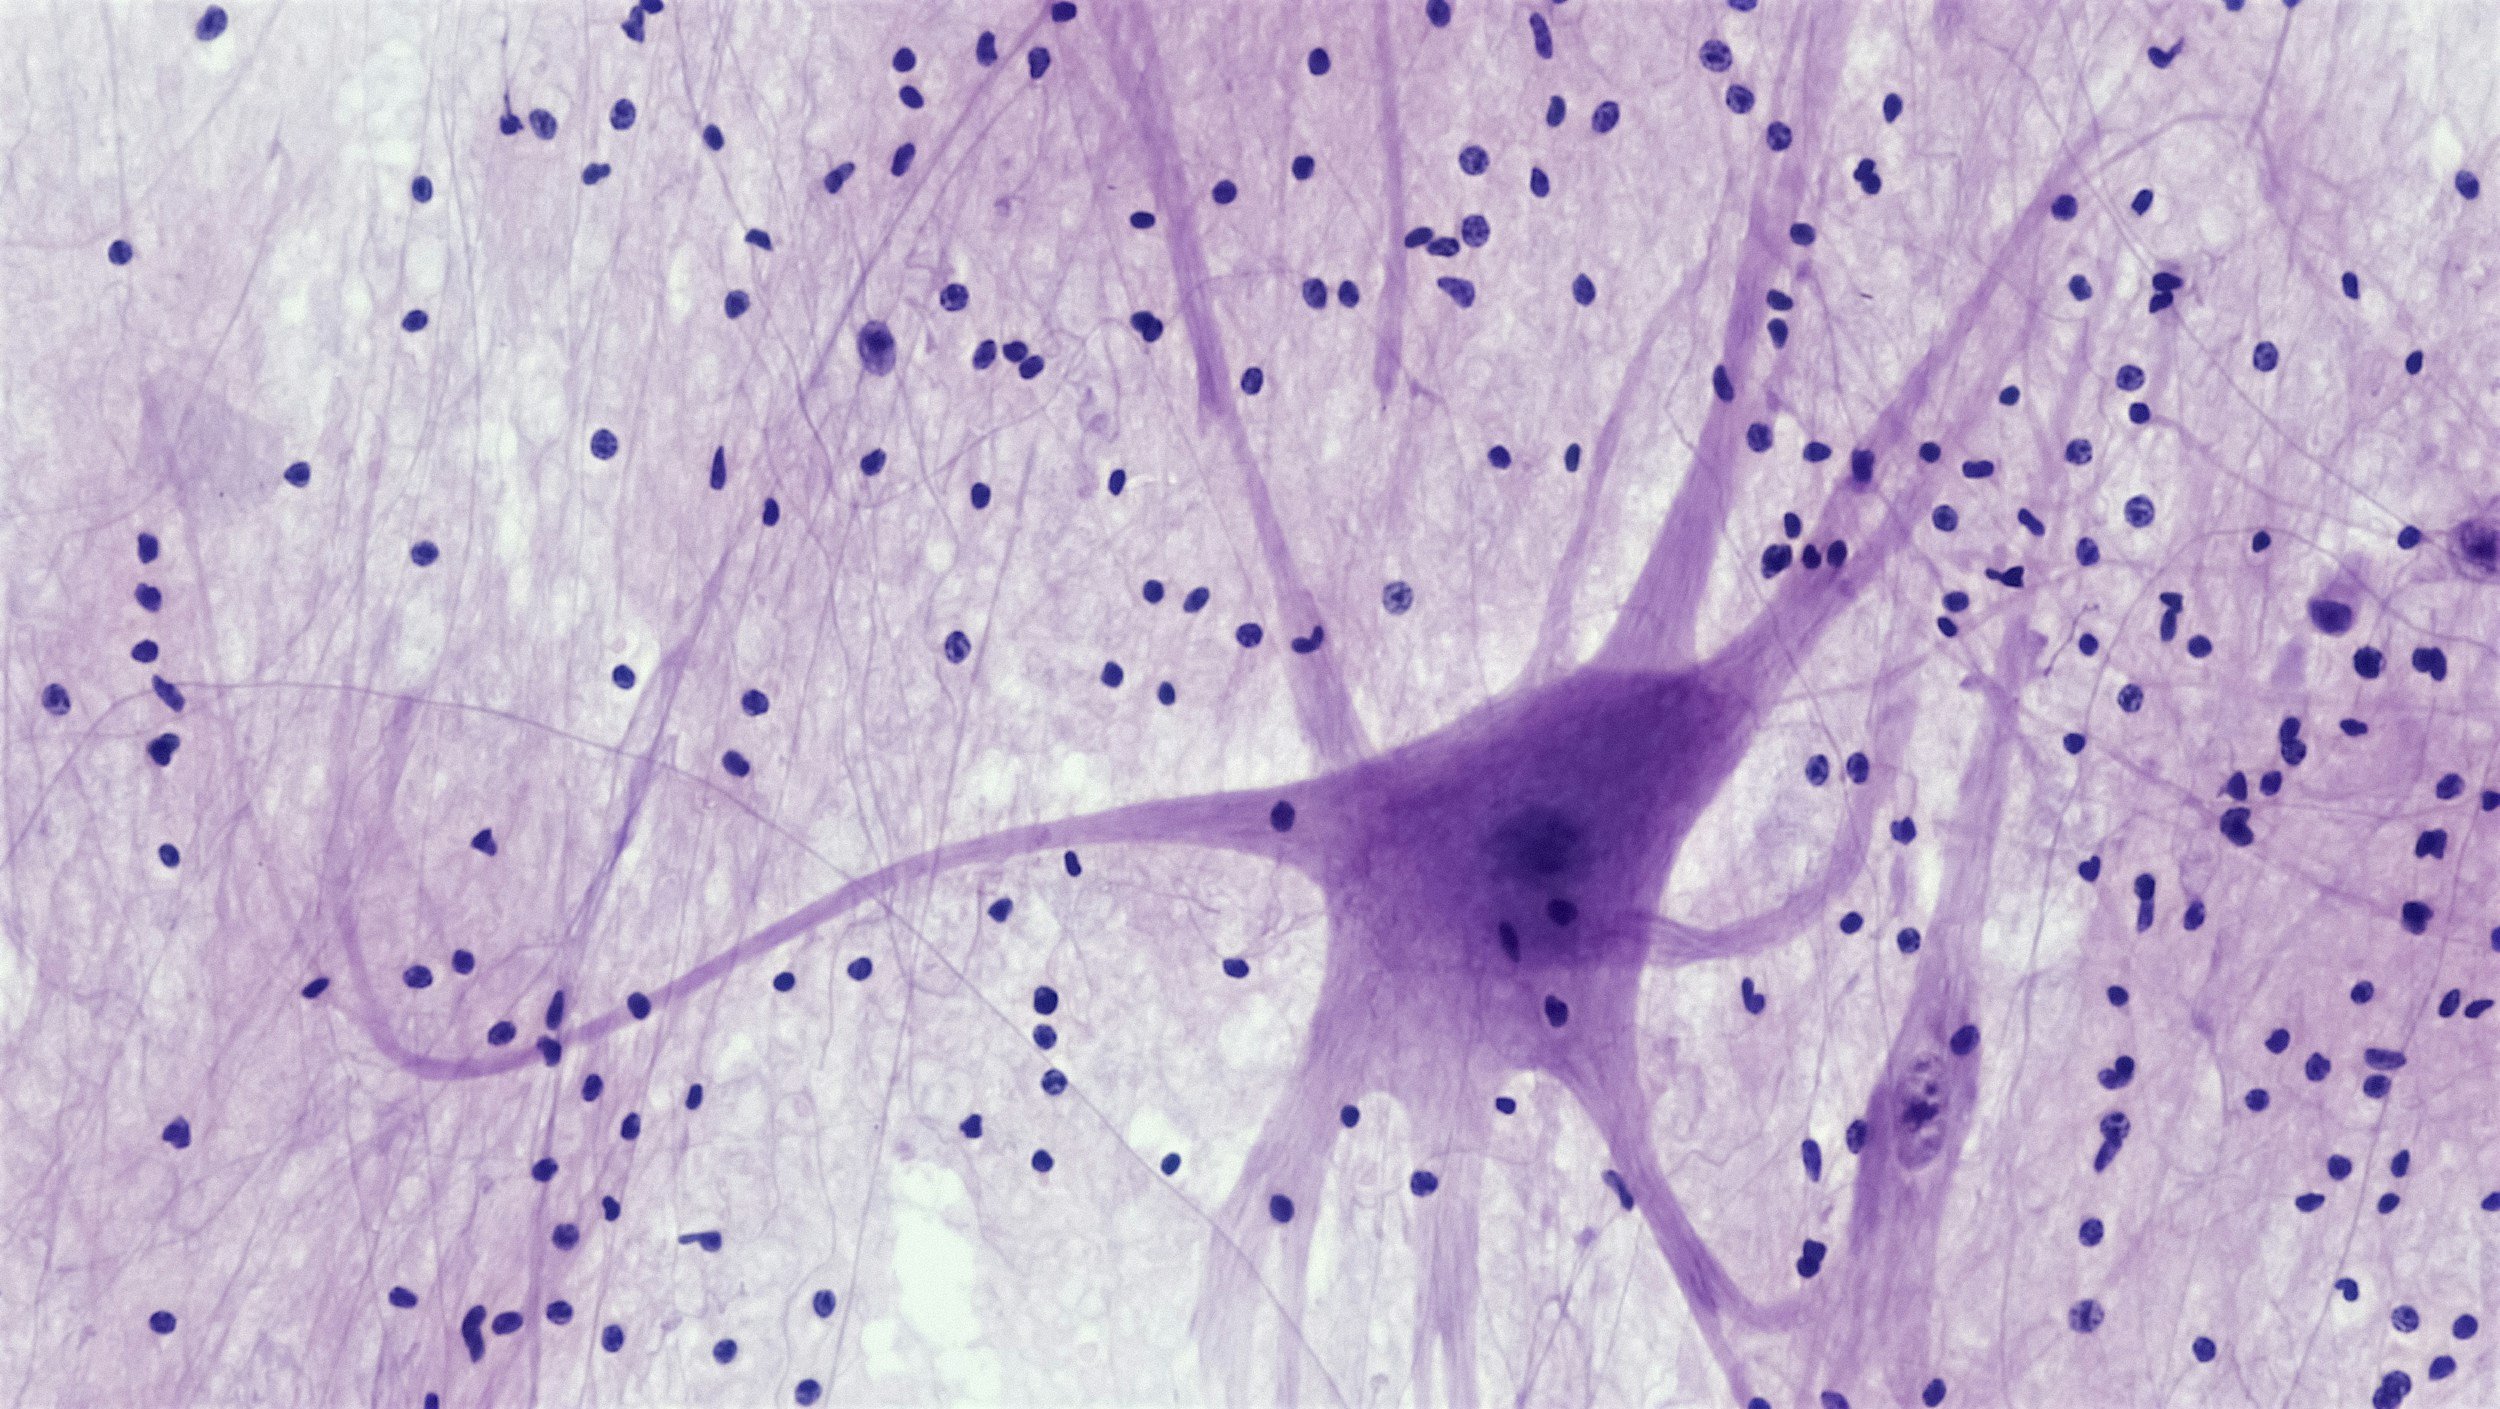

Think of your brain as a really sophisticated security system. Deep inside, in a region called the amygdala (pronounced ah-MIG-duh-lah), there's a tiny structure that acts like a smoke detector. The moment it senses danger like a loud noise, a threatening face, even a smell linked to a bad memory — it fires an alarm.

These aren't choices, they're automatic, survival-level responses that fire before your thinking brain ever gets a chance to weigh in. Think of it like a futuristic force field: it detects and responds to a threat before the threat even appears on your radar. The prefrontal cortex, the part of your brain responsible for reasoning, logic, and decision-making, essentially goes offline the moment the alarm sounds. Which is why you can't argue someone out of a panic response, and why telling a person to "just calm down" when their amygdala is activated is akin to shouting instructions at a force field. The system isn't listening to words right now. It's in full protection mode.

Research Note: Neuroscientist Joseph LeDoux's foundational work on the amygdala showed that fear responses travel a "low road" (a fast, direct neural pathway) that completely bypasses conscious thought. This is why trauma reactions can feel so out of control because they literally are. (LeDoux, J.E. The Emotional Brain, 1996; Neuron review 2015)